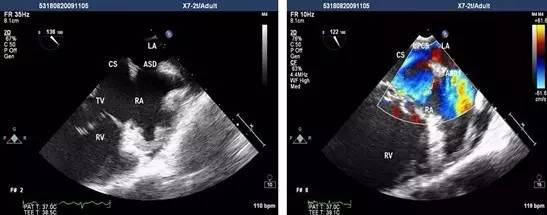

经食管超声心动图是将超声探头置入食管内,从心脏的后方向前近距离探查其深部结构,避免了胸壁、肺气等因素的干扰,故可显示出清晰的图像,提高对心血管疾病诊断的敏感性和可靠性。

为什么经食道超声心动图就能发现心房血栓呢?因为食管位于左心房后面,绝大部分人食管与左房后壁都有接触。

通过食管置入超声探头,就能很直观的从左心房后面看到心房里面的结构,能够看清心房、心耳内有无血栓。

而如果使用普通经胸的心脏彩超看心房,超声波需要穿过皮肤、肌肉、骨骼、肺等策划,就很难分辨清楚心房内有无血栓。